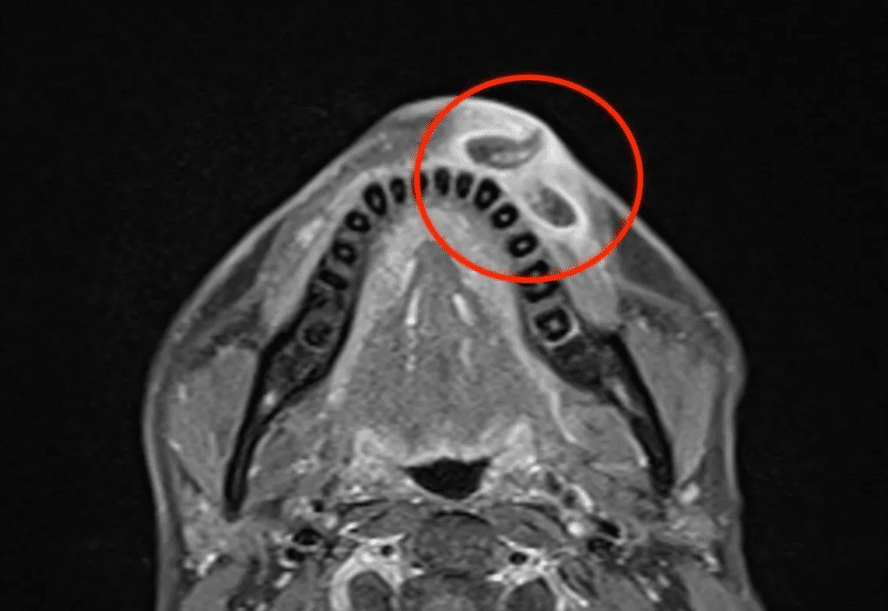

สำหรับคนไข้รายนี้ เมื่อตรวจอาการในฐานะผู้ป่วยนอก พบว่าที่บาดแผลมีการหลั่งสารอย่างต่อเนื่อง และมีลักษณะการเคลื่อนไหวของอะไรบางอย่างด้านใน แพทย์จึงลองบีบแผล แต่ผู้ป่วยทนความเจ็บปวดไม่ไหว ทำให้ต้องรับเข้ามาเป็นผู้ป่วยใน และทำการวางยาสลบในห้องผ่าตัด ก่อนจะค่อย ๆ คีบหนอนทั้ง 3 ตัวออกมา ซึ่งผู้ป่วยต้องพักฟื้น 1 คืน จึงจะกลับบ้านได้

การผ่าตัดใช้เวลาทั้งสิ้น 15 นาที โดยแพทย์สามารถดึงปรสิต 3 ตัวออกมาได้สำเร็จ ก่อนจะส่งไปตรวจต่อที่ห้องวิจัย กระทั่งได้รับการยืนยันว่า มันคือตัวอ่อนของแมลงหางม้า.